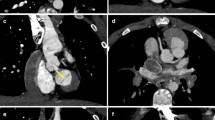

An 8-month-old boy with tetralogy of Fallot. Prospective ECG-triggering DSCT was performed at 80 kV and 60 mAs (effective dose, 0.29 mSv). (a) Ventricular septal defect (VSD) and overriding aorta on the reformatted images. (b) Thick-section oblique sagittal MIP image during systole shows critical stenosis of the right ventricular outflow tract (RVOT). RCA = right coronary artery, RV = right ventricle, LV = left ventricle, Ao = aorta, MPA = main pulmonary artery, LPA = right pulmonary artery

A 1-year-old boy with tetralogy of Fallot. Prospective ECG-triggering DSCT was performed at 80 kV and 70 mAs (effective dose, 0.38 mSv). (a) Thick-section oblique sagittal MIP image shows critical stenosis of the pulmonary valve (white arrow). (b) Oblique coronal multiplanar reformatted image shows patent ductus arteriosus (PDA) between aortic arch (Ar) and left pulmonary artery (LPA). Note stenosis of the proximal LPA (black arrow). RV = right ventricle, MPA = main pulmonary artery, RPA = right pulmonary artery

A 14-month-old girl with coarctation of the aorta. Prospective ECG-triggering DSCT was performed at 80 kV and 80 mAs (effective dose, 0.41 mSv). (a) Multiplanar reformatted image shows simultaneously the atrial septum defect (ASD) and muscular ventricular septal defect (VSD) accompanied by coarctation of the aorta. (b) Volume-rendered image (posterior view) demonstrates narrowing of the aortic isthmus (arrow). RA = right atrium, LA = left atrium, RV = right ventricle, LV = left ventricle, AA = ascending aorta, Ar = aortic arch, DA = descending aorta, LSA = left subclavian artery, RSA = right subclavian artery